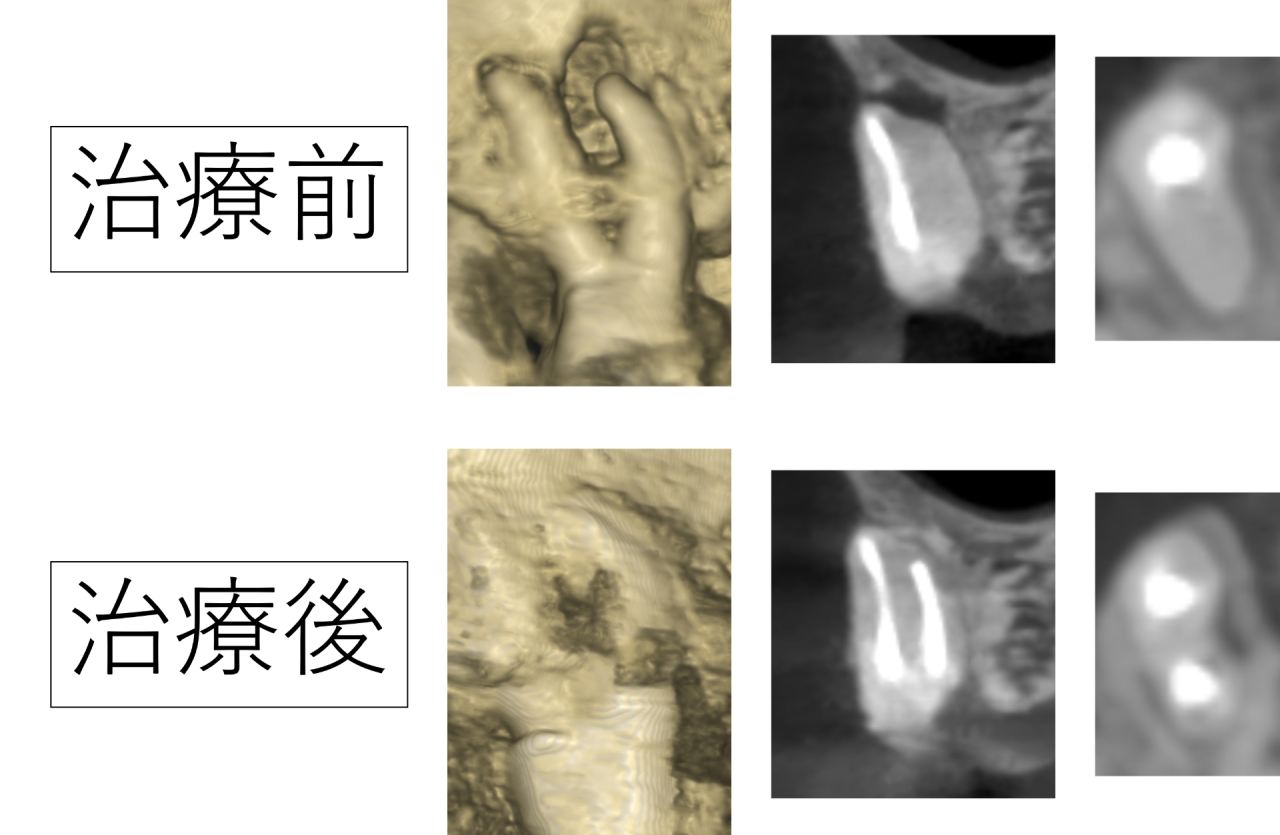

今回の右上の奥歯ですが、CTを撮影すると根っこに病気ができており、顎の骨が大きく貫通している状態でした。治療を受けて1年たっているとのことでしたが、この状態を見る限り、治療に不備があることが予想されました。

今回の症例では、詳しく確認した結果、根の中に神経(汚染組織)が取り残されていると予想されました。この取り残しが感染・炎症の元となり、治療後も痛みが続いていたと考えられます。

根の解剖学の話になりますが、神経は歯の根の真ん中にあるのが基本です。根の真ん中にない場合、一つの根に複数の神経があると予想されます。

病気がある根は真ん中に神経があるわけでなく、端に寄っていたため神経の取り残しが疑われました。

CTで得られた情報を元に、顕微鏡(マイクロスコープ)を見ながら慎重に器具で探していくと、予想通り取り残された神経が見つかりました。取り残された神経が感染し腐敗して炎症を起こし、痛みや骨が溶ける原因となっていたのです。

痛みはなくなり、骨が再生した

治療後かぶせ物を行い4年経過していますが、痛みもなく非常に良好です。

溶けていた顎の骨も再生し、空いていた穴が埋まりました。